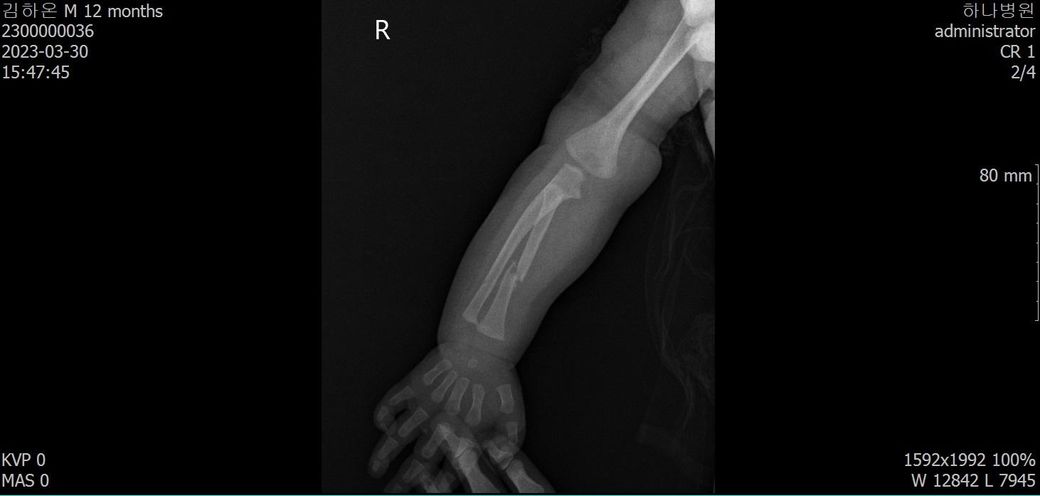

다름이 아니라, 첨부드린 엑스레이(X-ray) 사진처럼 골절 사실을 알게 되고 골절 발생 시점 대략적으로나마 추정시기를 파악하려고 문의 드리게 되었습니다

1) 3월 30일 촬영한 X-ray만으로 정확한 골절 시기를 100% 특정하는 데에는 한계가 있다는 점 충분히 인지하고 있기에 촬영날짜 기준으로 대략적으로 어느정도 시점에서 발생되었을 것으로 추측(ex 당일, 7~10일전, 7~14일 전, 10일 ~ 20일전, 14일 ~ 30일전 등등등)되는지 이해하고 싶습니다.

• 2번 째 사진

엑스레이상 골절선이 뚜렷한 시기는 1주, 골막 반응이 보여진다면 1~2주, 연골성 가골이 형성되는 시점은 2~3주, 가골이 명확해지면 3~6주 정도로 추정할 수 있습니다.

다만 "3월 30일 영상에서 골절선이 비교적 뚜렷하고, 4월 10일에 상당한 가골(callus)이 형성"된 점을 종합하면 "골절은 3/30 당일보다는 최소 수일~2주 이상 이전에 발생했을 가능성이 높습니다."

올려주신 사진을 참고하였을 때 3월말에는 켈로스(가골)형성이, 4월에는 유합이 진행되고 있는 상태를 고려해볼 수 있겠습니다.

회복 경과를 바탕으로 대략적인 시점을 고려하여 보자면 3월 말 시점에서 약15-20일 정도의 기간을 골절 발생시기로 의심해볼 수 있겠지만, 정확한 소견은 관련 전문의의 의견을 들어보심이 좋습니다.